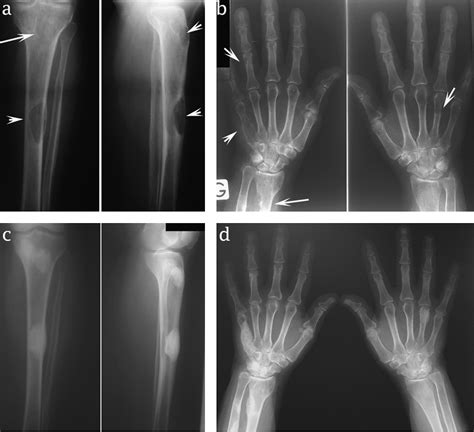

• Pre-existing bone disease: Evidence of osteoporosis or osteitis fibrosa cystica on imaging (like X-rays or bone density scans) indicates significant skeletal mineral loss.

While blood tests are the primary diagnostic tool, imaging studies performed before surgery are often used to predict the risk. An elevated preoperative ALP, coupled with radiologic evidence of severe bone demineralization, alerts the surgical team to prepare for aggressive postoperative mineral replacement therapy.